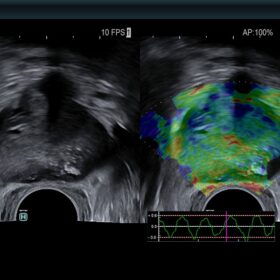

Ultrasound ARIETTA 750 VE – Image Gallery and Videos

Cardio 2D and Color mode

Women’s Health

Be equipped for breast pathologies and fetal assessment.

- Highly sensitive colour mode to replace contrast agents

- Doppler measurements from two gates in same heart cycle

- Advanced vessel and blood flow analysis tools

- Advanced cardiac reporting workstation

Urology

Be precise in biopsy, transrectal or transabdominal procedures.

- Dedicated probes for optimal needle guidance

- Advanced Fusion Imaging features

- Advanced Elastography features

- Contrast Imaging